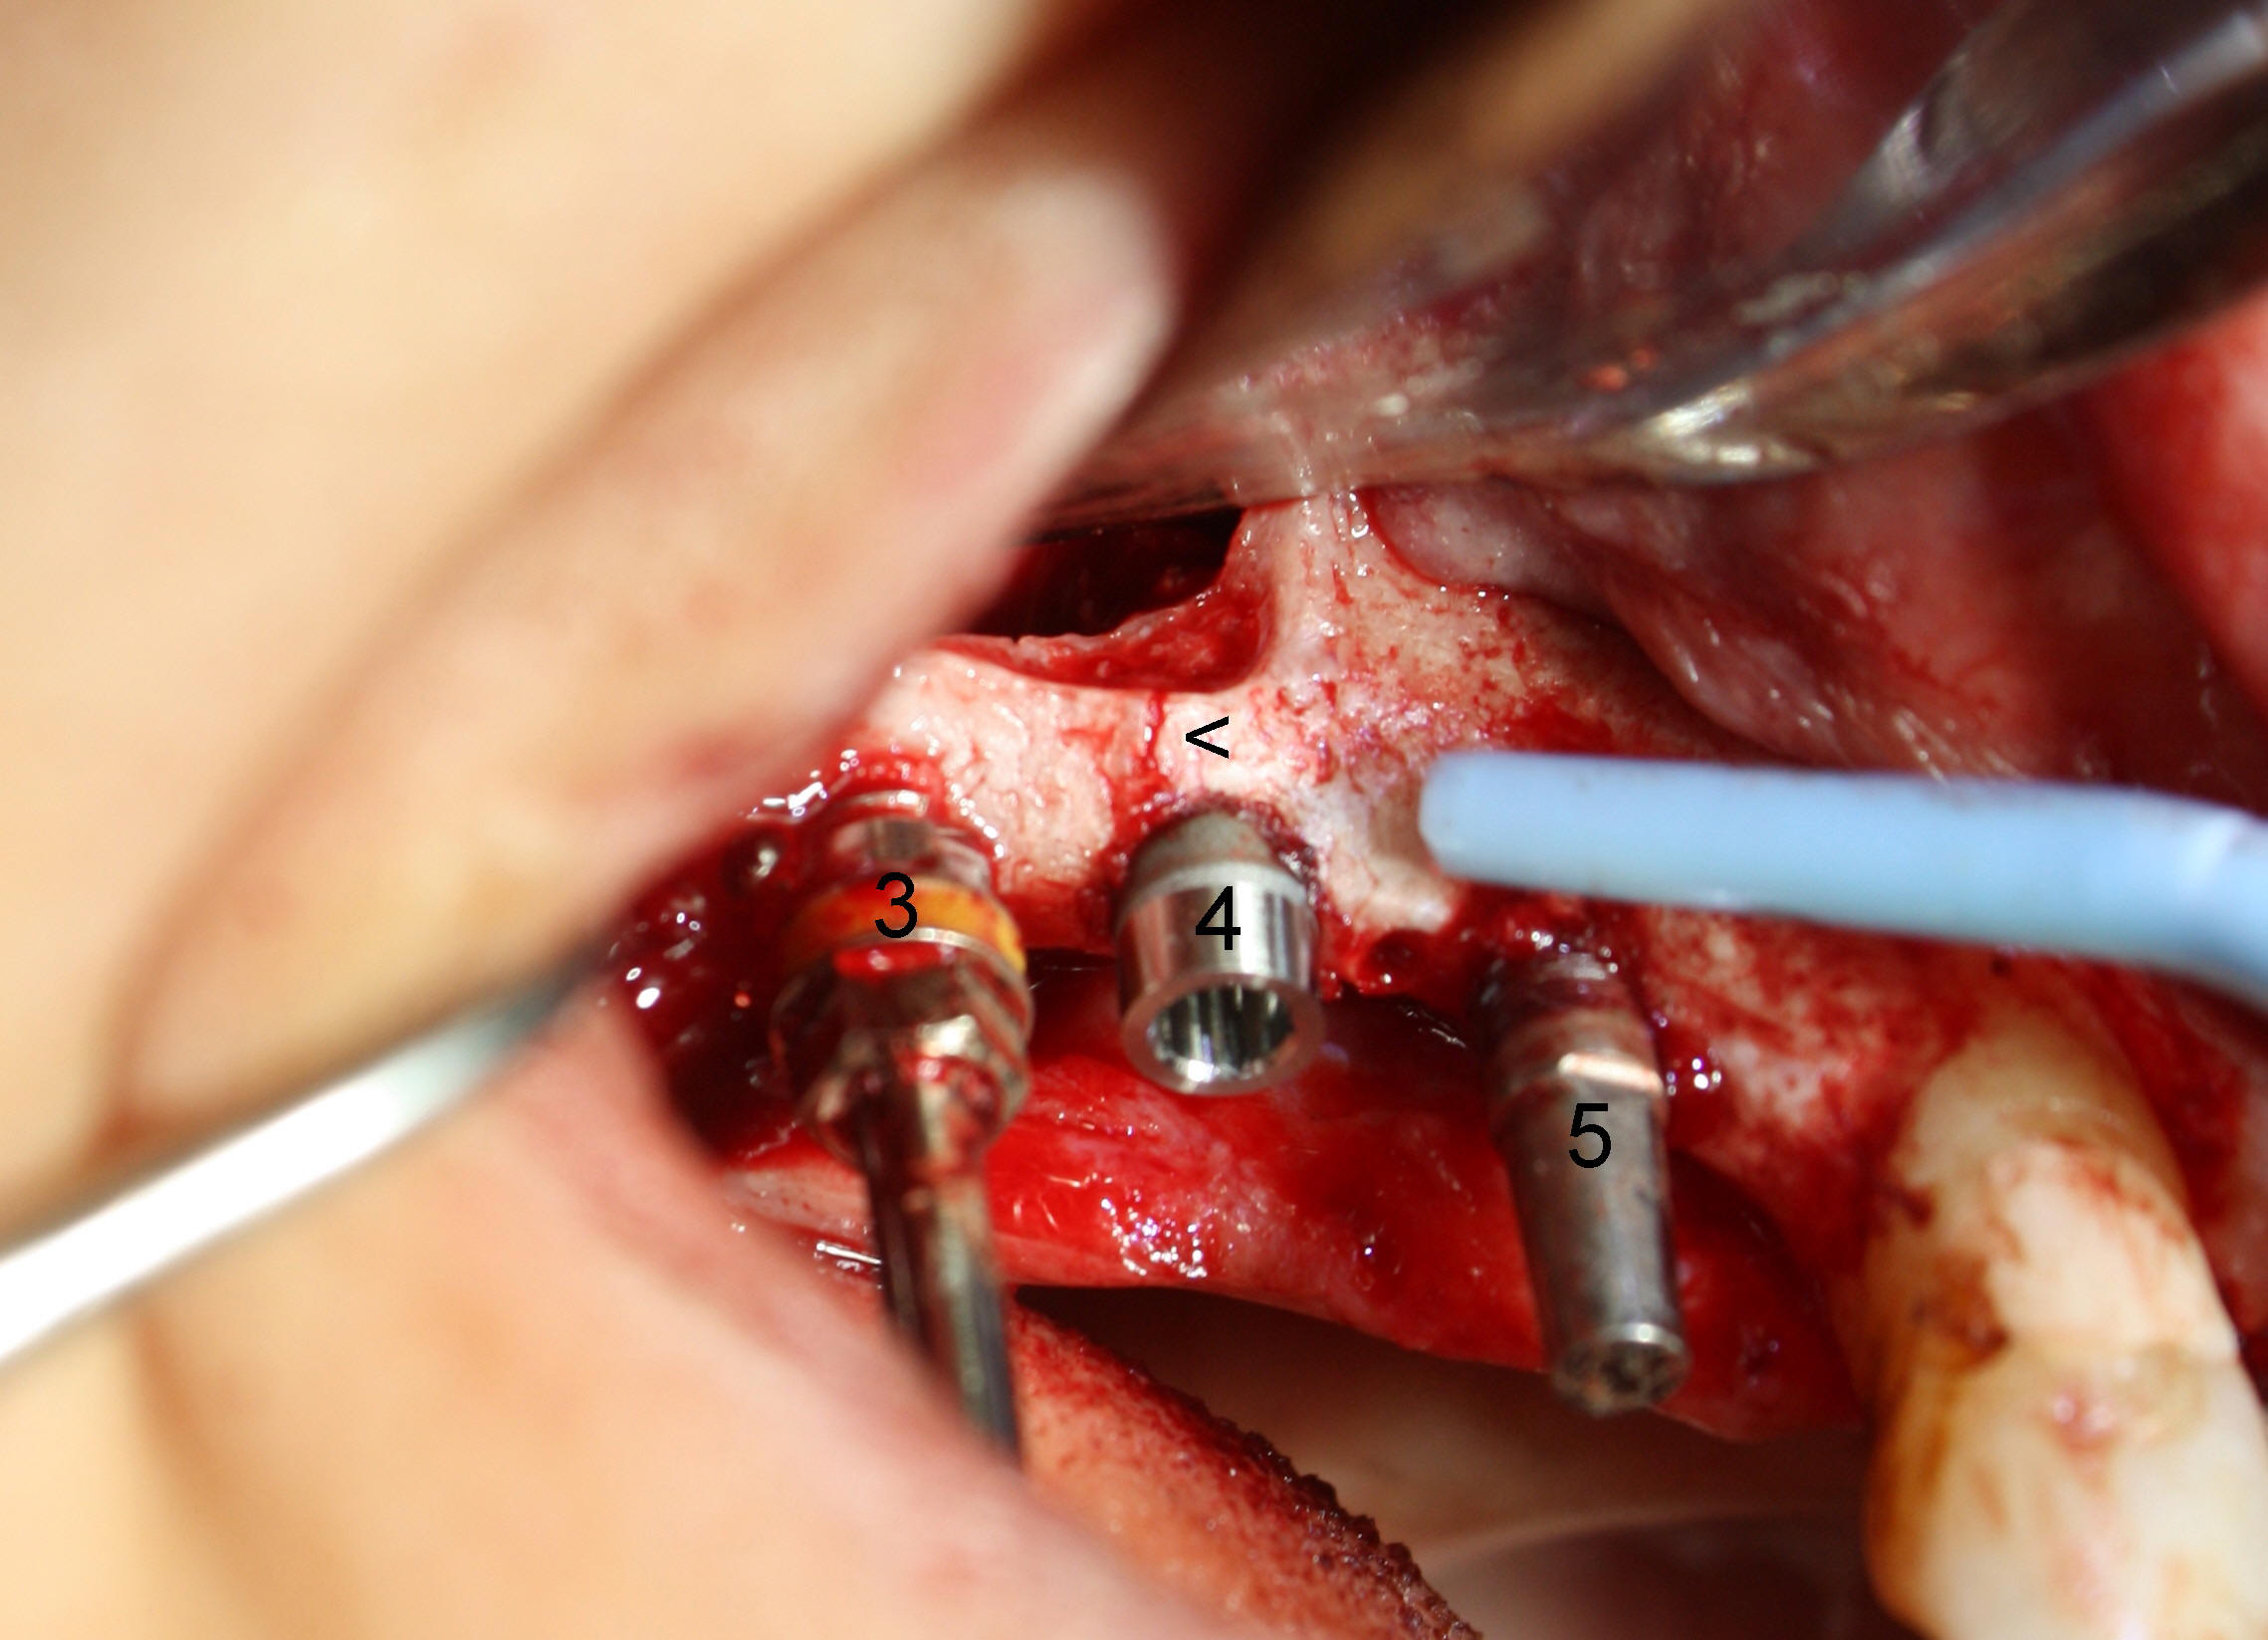

When the sinus membrane is lifted, osteotomies are made at the sites of #2-5 (Fig.2) with insertion of taps at #2 and 3 and reamers at #4 and 5.

A 3.5x17 mm one-piece implant is placed at #5 and a 4x11 mm two-piece at #4 with crack line buccally (Fig.3 <), while a 4.5x11 mm tap is in place at #3.

Fig.4 shows 4 implants in place with implant apex sticking into the sinus (>, which will be covered by bone graft). Fig.5 is a PA taken post bone graft, while Fig.6 is a section of panoramic X-ray showing the boundary of bone graft (arrowheads) after cementation of a provisional bridge. The latter satisfies the patient's request for cosmetics.